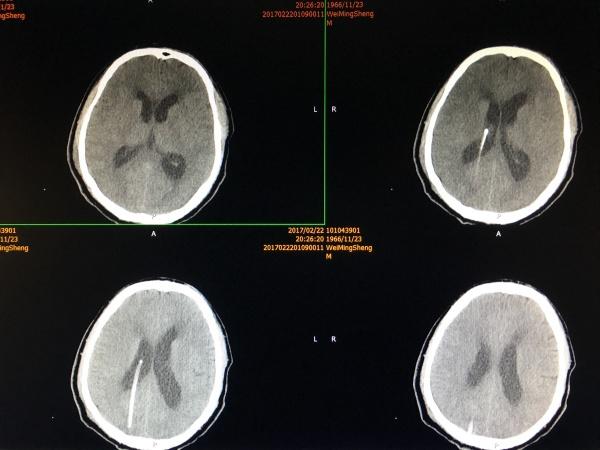

手术顺利,术后CT如上图所示,患者有谵妄症状,已予以对症处理,现患者有轻微水平眼震,较前明显好转. 手术很大,很成功,并不只是神经外科一家之功,麻醉师的强力支持绝对是重中之重!尤其是关乎脑干的手术!